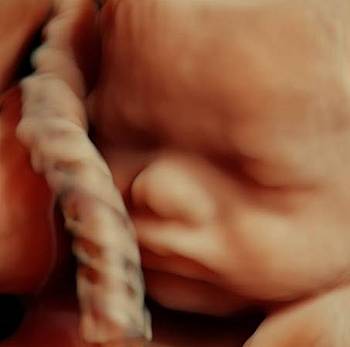

Bestimmung des kindlichen Wachstums (es werden immer Kopf- und Bauchumfang sowie Oberschenkellänge des Feten gemessen). Kontrolle von Plazentasitz und -auffälligkeiten. Messung von Harn, Blutdruck und Gewicht.

Cervixultraschall zur Bestimmung der Gebärmutterhalslänge, Wachstumskontrolle des Kindes. Messung der Nabelschnurdurchblutung zur Überprüfung der kindlichen Versorgung.

Wellbeingschall mit Wachstums- und Gewichtskontrolle des Feten, Bestimmung von Fruchtwassermenge, Plazentasitz und –struktur sowie Kontrolle von Nabelschnurdurchblutung, Harn und Blutdruck.

Kontrolle der Kindslage, des Wachstums, der Fruchtwassermenge und Nabelschnurdurchblutung.